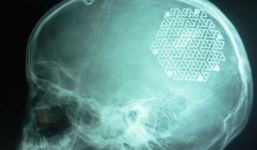

Lắp hộp sọ bằng kim loại cho bé gái 9 tuổi ở Quảng Bình